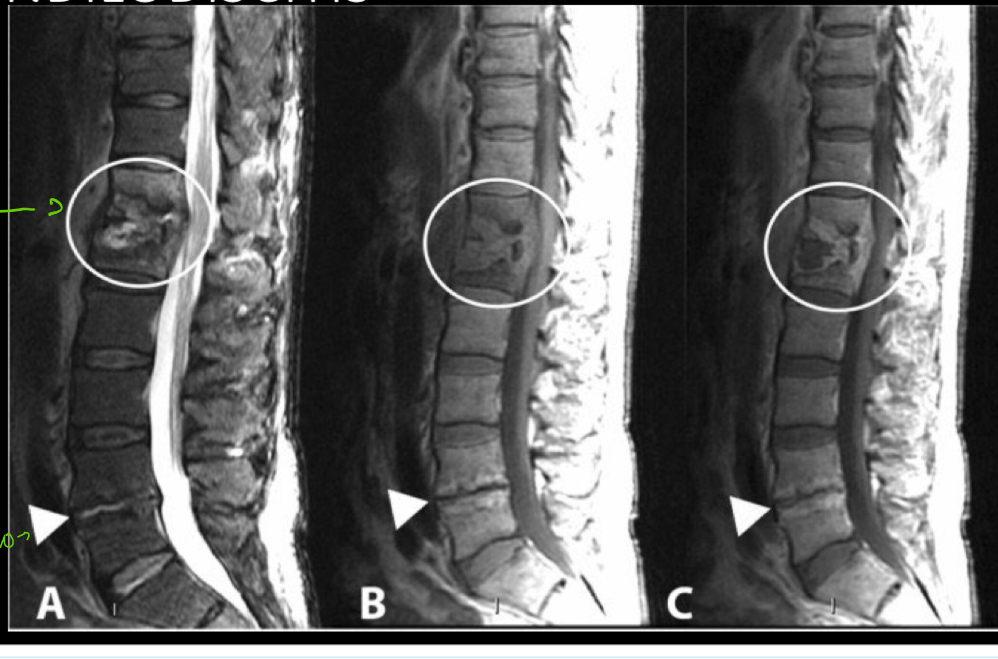

Q

Q señala la de arriba y la de abajo

A

arriba: absceso hiperintenso entre vertebras: pus

Abajo: proceso degenerativo